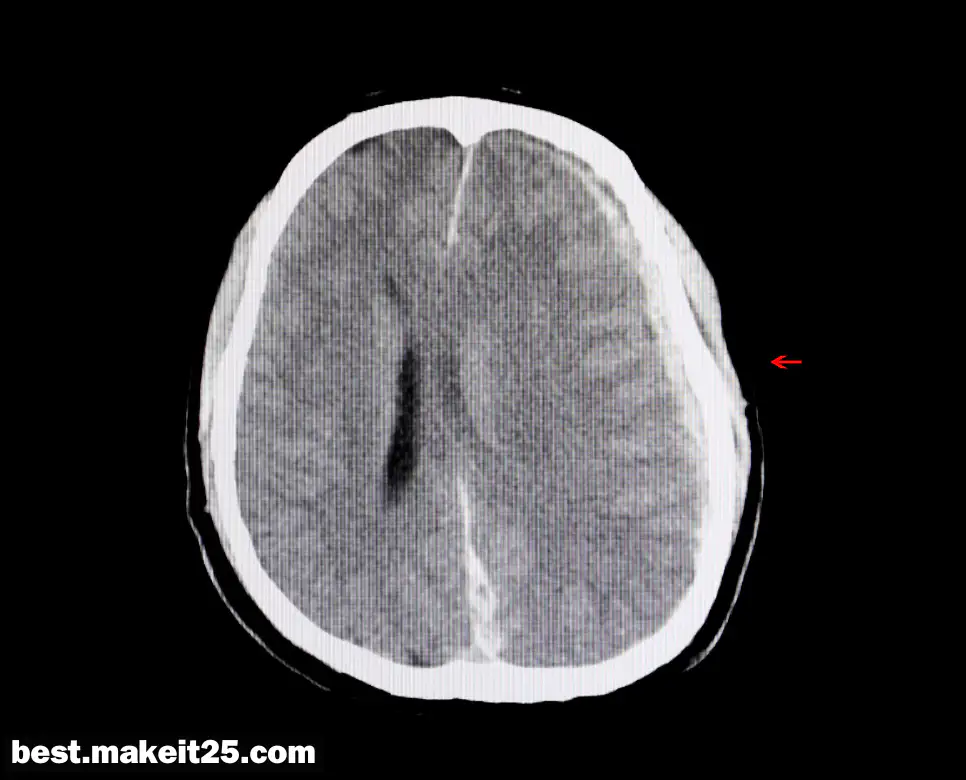

‘IVH’는 Intraventricular Hemorrhage의 약자로, 한국어로는 뇌실내출혈을 의미합니다. 이는 뇌실 내부에서 발생하는 출혈로, 뇌척수액(CSF)이 존재하는 뇌실 공간에서 혈액이 새어 나오는 상태를 말합니다. 뇌실내출혈은 외상, 동맥류, 종양, 혈관 기형 등 다양한 원인에 의해 발생할 수 있습니다.

- 증상: 두통, 오심, 구토, 발작, 의식 저하 등 다양한 신경학적 증상을 유발할 수 있습니다.

- 진단: 뇌실내출혈은 두부 초음파, CT, MRI 등의 영상 진단을 통해 확인할 수 있습니다.

- 치료: 수술적 치료 없이 EVD(외부 뇌실 배액)를 통한 배액, 뇌압 관리 등이 이루어질 수 있습니다.

IVH는 뇌의 중요한 부위에서 발생하는 출혈로, 신속한 진단과 적절한 치료가 필요한 심각한 상태입니다. 특히 조산아에게서 더 자주 발생하며, 이들에게는 특별한 주의가 요구됩니다.